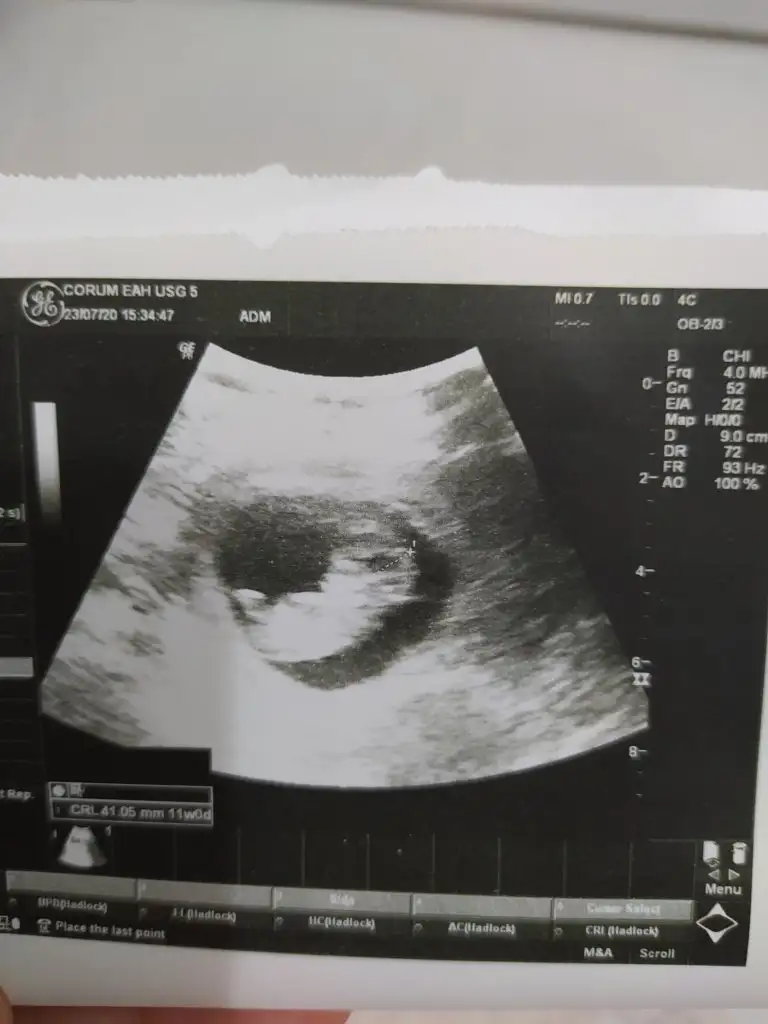

İkra hanım banada bir yorum yapar mısınız 12 haftalık

Eklentiler

• E6E77655-D0AC-47E5-B384-92C571E57F66.webp

E6E77655-D0AC-47E5-B384-92C571E57F66.webp

22,2 KB · Görüntüleme: 75